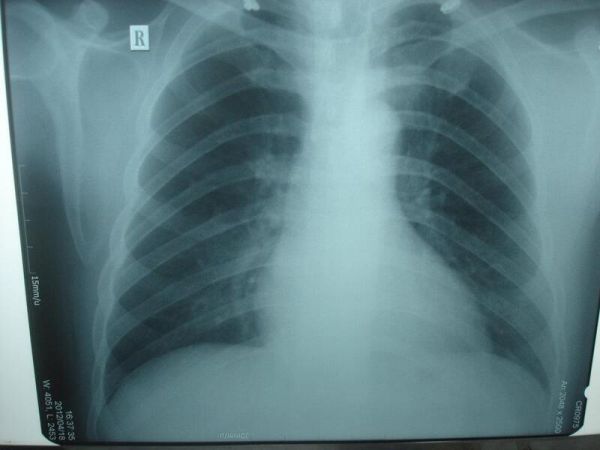

X-quang ngực là hình ảnh của ngực cho thấy tim, phổi, đường thở, mạch máu và các hạch bạch huyết. X-quang ngực cũng cho thấy xương cột sống và ngực, bao gồm xương ức, xương sườn, xương đòn và phần trên của cột sống. X-quang ngực là thủ thuật hình ảnh phổ biến nhất hoặc X-quang được sử dụng để tìm các vấn đề bên trong ngực.

X-quang ngực có thể giúp tìm thấy một số vấn đề với các cơ quan và cấu trúc bên trong ngực. Thông thường hai bức ảnh được chụp, một từ phía sau ngực và một từ phía bên. Trong trường hợp khẩn cấp khi chỉ chụp một bức ảnh X quang, chế độ xem trước thường được thực hiện. Các bác sĩ có thể không phải lúc nào cũng có được thông tin họ cần từ X-quang ngực để tìm ra nguyên nhân của vấn đề. Nếu kết quả chụp X-quang ngực không bình thường hoặc không cung cấp đủ thông tin về vấn đề ngực, có thể thực hiện các X-quang cụ thể hơn hoặc các thủ thuật khác, chẳng hạn như chụp cắt lớp vi tính (CT), siêu âm, siêu âm tim hoặc MRI.

X-quang ngực là hình ảnh của ngực để thấy tim, phổi, đường thở, mạch máu và các hạch bạch huyết. X-quang ngực cũng cho thấy xương ngực, bao gồm xương ức, xương sườn, xương đòn và phần trên của cột sống.

Bình thường

Hình phổi trông bình thường về kích thước và hình dạng, và các mô phổi trông bình thường.

Không có sự tăng trưởng hoặc khối khác có thể được nhìn thấy trong phổi.

Các không gian màng phổi (không gian xung quanh phổi) cũng trông bình thường.

Tim trông bình thường về kích thước, hình dạng và mô tim trông bình thường.

Các mạch máu dẫn đến và từ tim cũng bình thường về kích thước, hình dạng và ngoại hình.

Xương bao gồm cột sống và xương sườn trông bình thường.

Cơ hoành trông bình thường về hình dạng và vị trí.

Không có dịch hoặc không khí được nhìn thấy, và không có vật thể lạ được nhìn thấy.

Tất cả các ống, ống thông hoặc các thiết bị y tế khác đều ở đúng vị trí của chúng trong ngực.

Bất thường

Nhiễm trùng, như viêm phổi hoặc bệnh lao.

Các vấn đề như khối u, chấn thương hoặc một tình trạng như phù do suy tim có thể được nhìn thấy.

Trong một số trường hợp, có thể cần thêm tia X hoặc các xét nghiệm khác để thấy rõ vấn đề.

Có thể nhìn thấy một vấn đề như tim giãn có thể do tổn thương tim, bệnh van tim hoặc dịch xung quanh tim. Hoặc một vấn đề của các mạch máu, chẳng hạn như động mạch chủ giãn, phình động mạch hoặc xơ cứng động mạch (xơ vữa động mạch), được nhìn thấy.

Chất dịch được nhìn thấy trong phổi (phù phổi) hoặc xung quanh phổi (tràn dịch màng phổi), hoặc không khí được nhìn thấy trong các không gian xung quanh phổi (tràn khí màng phổi).

Xương gãy được nhìn thấy trong lồng xương sườn, xương đòn, vai hoặc cột sống.

Hạch to được nhìn thấy.

Một vật lạ được nhìn thấy trong thực quản, ống thở hoặc phổi.

Ống, ống thông hoặc thiết bị y tế khác có vẻ như nó đã di chuyển ra khỏi vị trí chính xác.